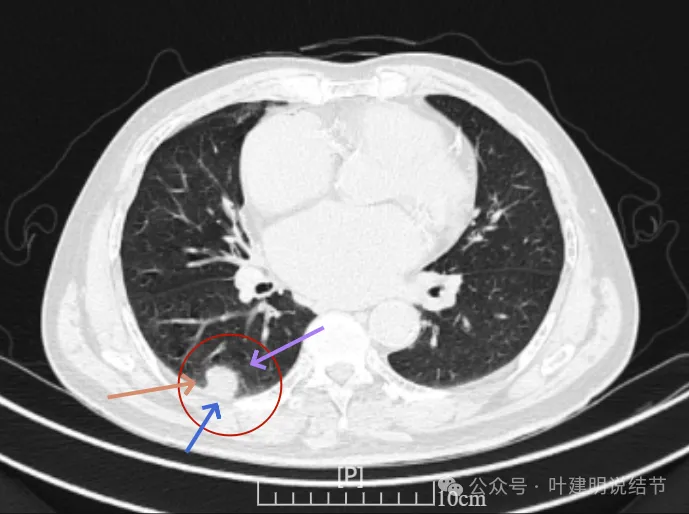

增强纵隔窗见病灶内部的密度好像低于周围区域,像坏死。

邻近胸膜无牵拉,灶内有低密度区,局部有点状液性密度。邻近胸膜较为广泛的增厚或胸膜反应。

病灶与胸膜接触面宽,病灶内部密度较低。